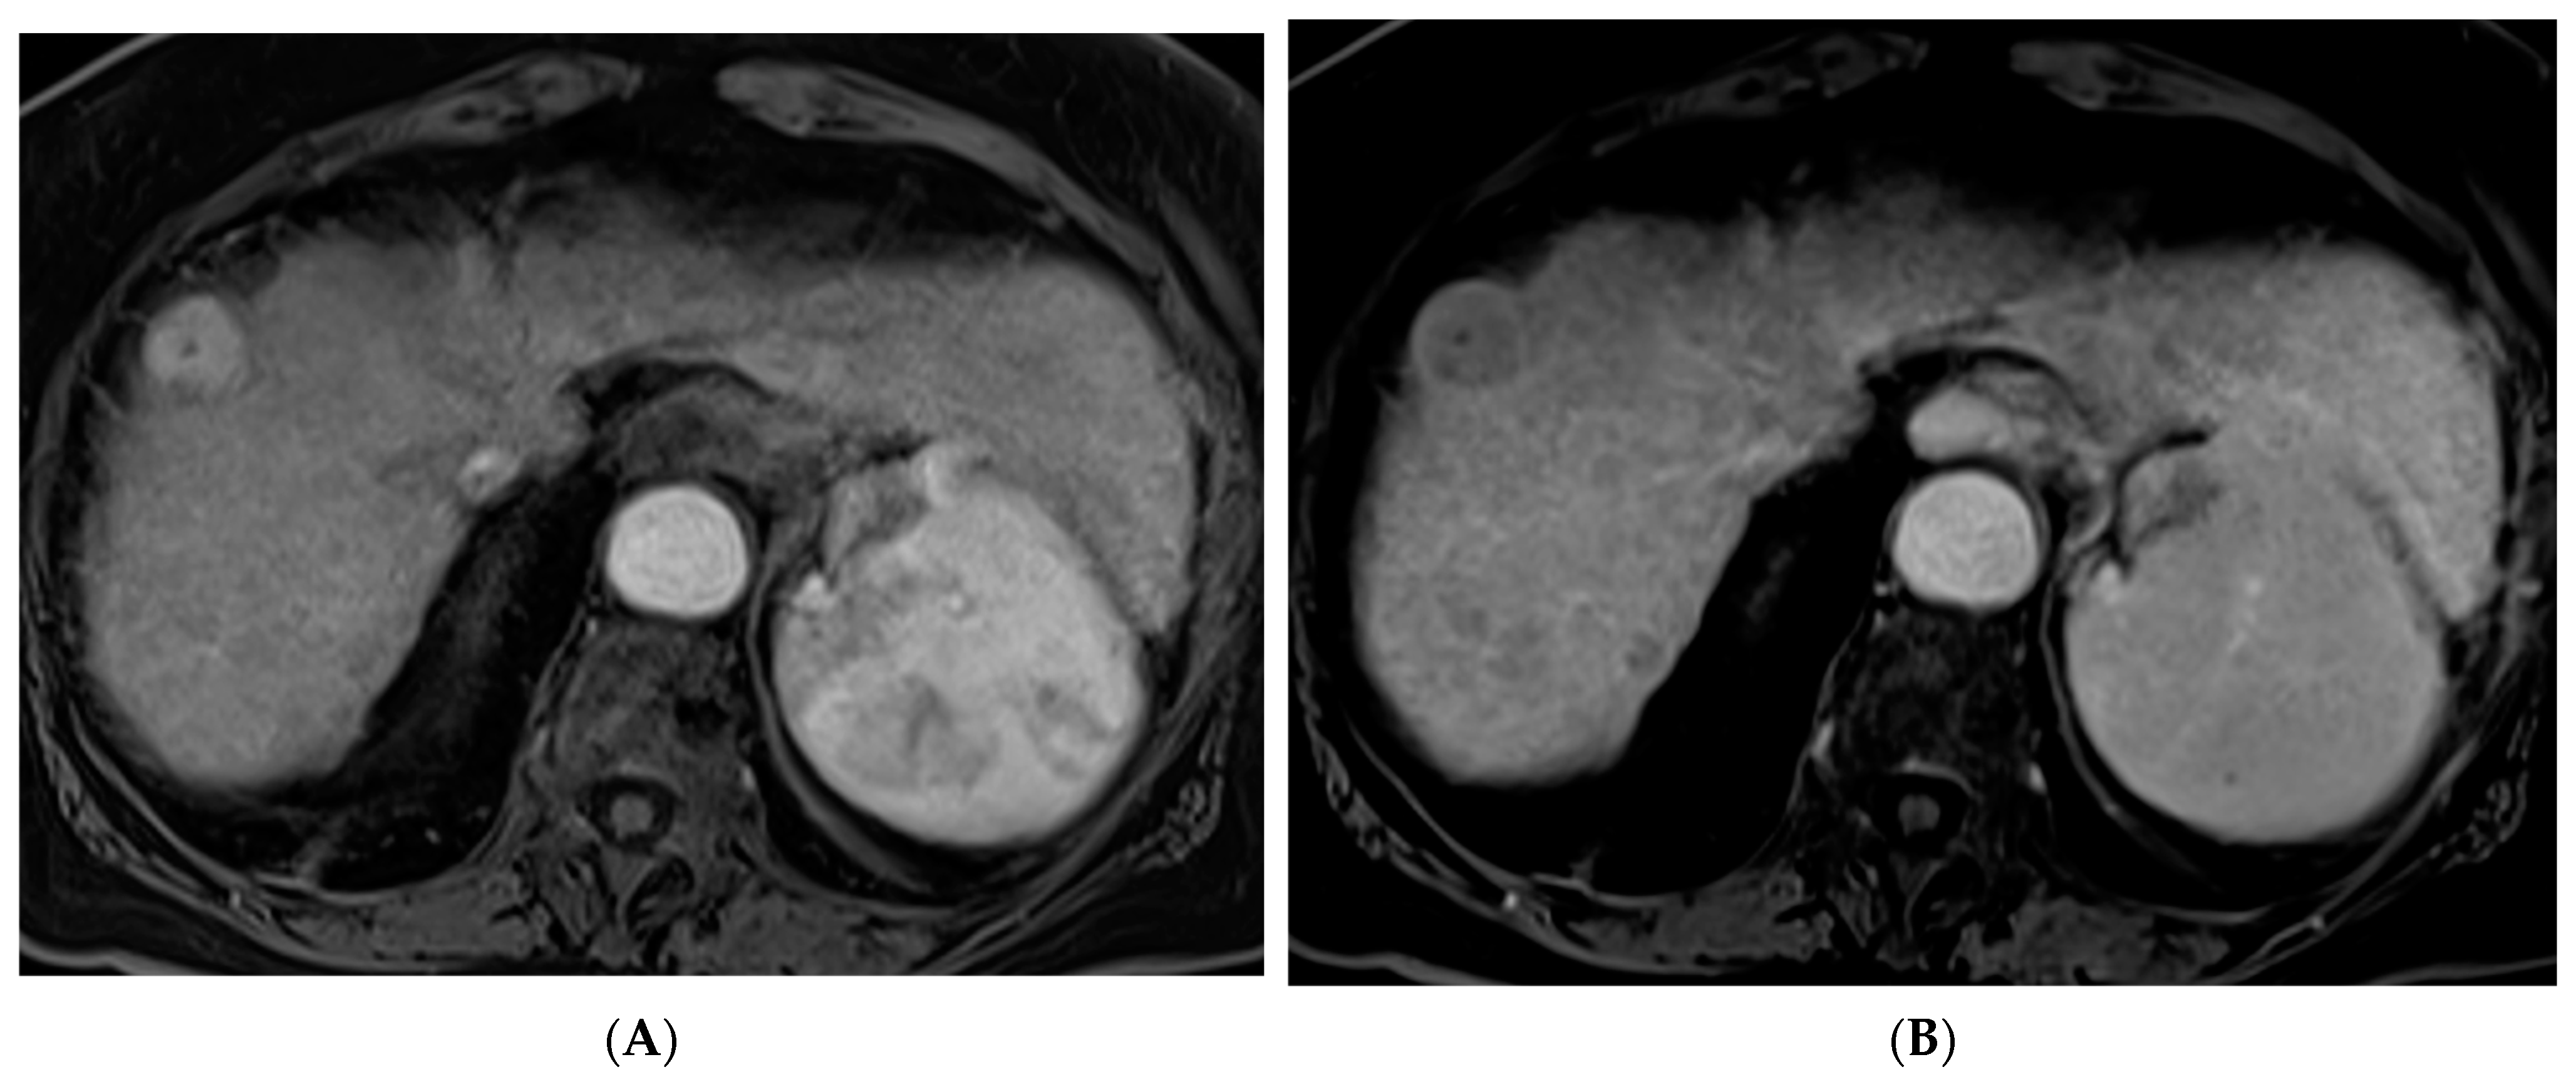

Figure 2.

88-year-old woman with HCC on a background of cirrhosis secondary to autoimmune hepatitis treated with conventional TACE. (A) Arterial phase MRI showing a 2.2 cm arterially enhancing lesion in hepatic segment 8. (B) Delayed phase MRI showing washout of the lesion. (C) Intraprocedural CTA demonstrating supply to the hypervascular lesion from the segment 8 arterial branch. (D) Post procedure non-contrast CT demonstrating the ethiodized oil deposition within the tumor and surrounding segment 8 parenchyma. (E) Follow up arterial phase MRI one month after treatment demonstrating no arterial enhancement within the treated lesion consistent with complete response.